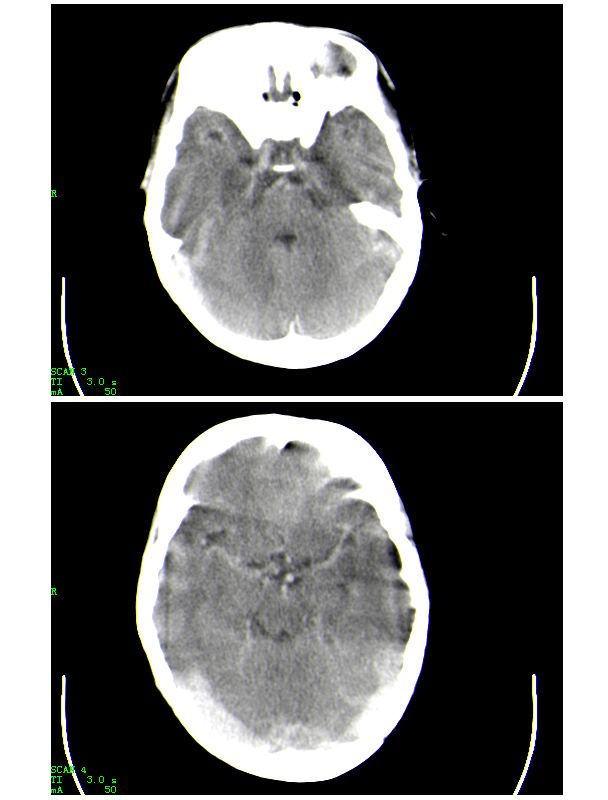

患者,男,15岁。发现心脏杂音12年。因心慌气短、胸闷等症状加重而就诊。急诊实验室检查:红细胞平均体积0.95,红细胞压积0.820,红细胞容积分布宽度0.166,红细胞数8.55x10^12/l,血红蛋白(hb)267g/l。就诊前及就诊期间无外伤史,未服用或注射高密度元素制剂,未行影像造影检查和增强检查。急诊ct平扫示:颅内血管系统边缘清楚,但其内密度明显均匀增高(ct值约73hu),高于脑实质密度,所见颅内脑沟显示边界清楚,脑脊液及脑实质密度属正常平扫密度范围(图1-4)。影像诊断:高血红蛋白脑血管致密改变。

说明:ct值的测定以纯水为0hu,随着水中成分的增加,液体对x线的吸收增加,进而ct值增高。人体血液中影响ct值的主要成分是有形成分红细胞和血浆中的蛋白质,尤其室含铁的hb,其占血液中蛋白质总量的大部分,亦是引起血液ct密度变化的主要因素。hb含量与ct值间具有相关性,noman等的研究表明hb含量每改变10g/l,相应ct值变化为1.86hu。而本例患者的hb高达267g/l,可以解释颅内血管ct值明显升高的原因。本病主要应与蛛网膜下腔出血相鉴别,鉴别要点:(1)本病的高密度血管网络旁仍见清晰、正常低密度脑脊液影;(2)临床没有急性颅内出血的症状何体征。